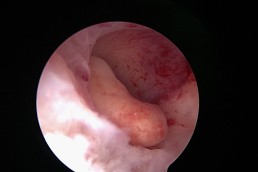

Aspectul normal al cavității uterine

În mod normal, cavitatea uterină are pereți netezi și este lipsită de fibroame, țesut cicatricial, malformații congenitale sau polipi (Fig.1). Simultan cu inspecția aspectului pereților uterini se vizualizează și originea trompelor uterine (dreaptă și stângă) – Fig. 2